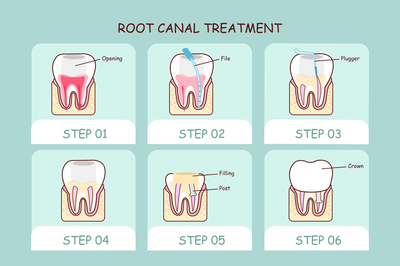

Hello: 1。牙疼的时候原则上是不允许拔牙的!主要是怕炎症扩散到间隙,但也有例外,比如牙痛,如果确定是牙髓炎早期,不涉及牙根,就可以摘除。2.以上拔牙只针对智齿,原则上除智齿外的牙齿都要尽量保留,疼痛可以通过“根管治疗”来解决。建议最好先找医生帮忙,再进行治疗。